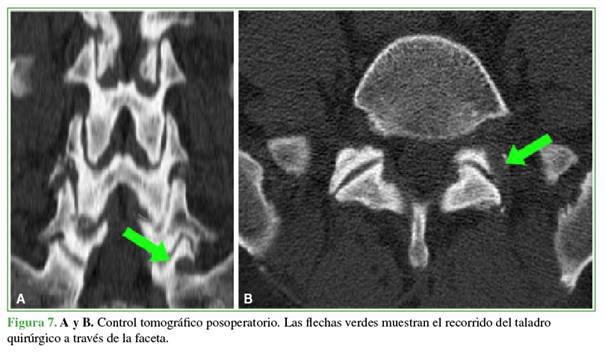

Discectomía endoscópica transfacetaria L5-S1

Bajo anestesia general, se coloca al paciente en decúbito prono. Mediante radioscopia directa en posición de frente, se marca con una aguja de 16 G en la punta de la faceta articular superior de S1. Se realiza una incisión cutánea de 8 mm y la apertura de la fascia lumbar. A continuación, se desciende la cánula de trabajo junto con el endoscopio. Se procede al fresado lateral de la faceta de la vértebra inferior con fresa diamantada. A medida que se genera el espacio en dirección medial y ventral, se desciende la cánula. Una vez localizada la cortical anterior de la faceta, se la reseca con una pinza Kerrison Rongeur de 3 mm. Luego, se efectúa un control radioscópico para confirmar la correcta dirección de trabajo (Figuras 5-7).